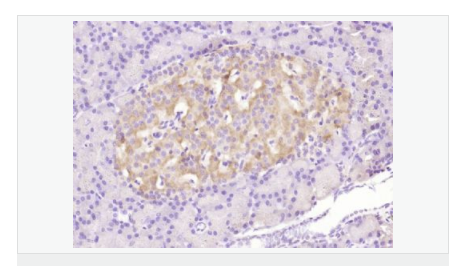

| 產(chǎn)品應用 | WB=1:500-2000 ELISA=1:5000-10000 IHC-P=1:100-500 Flow-Cyt=3μg /test (石蠟切片需做抗原修復) not yet tested in other applications. optimal dilutions/concentrations should be determined by the end user. |